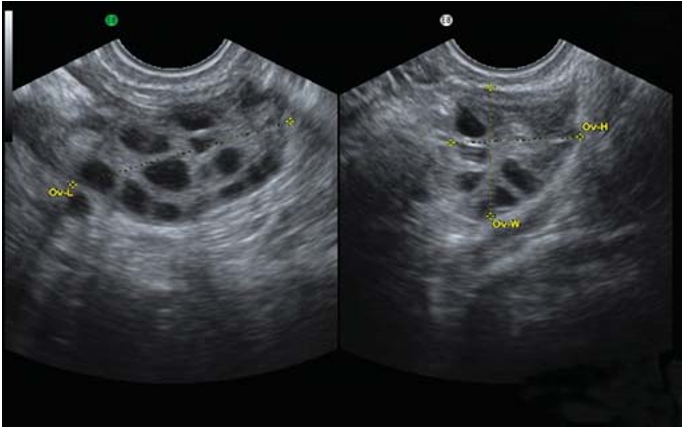

使用骨盆超音波,分為腹部跟陰道2種,通常使用陰道超音波來觀察卵巢,更加詳細。

✅卵巢超過10個以上卵泡

多囊性卵巢症患者,做超音波檢查時發現卵巢長出許多濾泡(內有卵子)。這些小囊大小約2~8mm,小囊數目每邊卵巢約十~一百個之間,但是都是不成熟的卵子,無法排出,進而導致無月經。